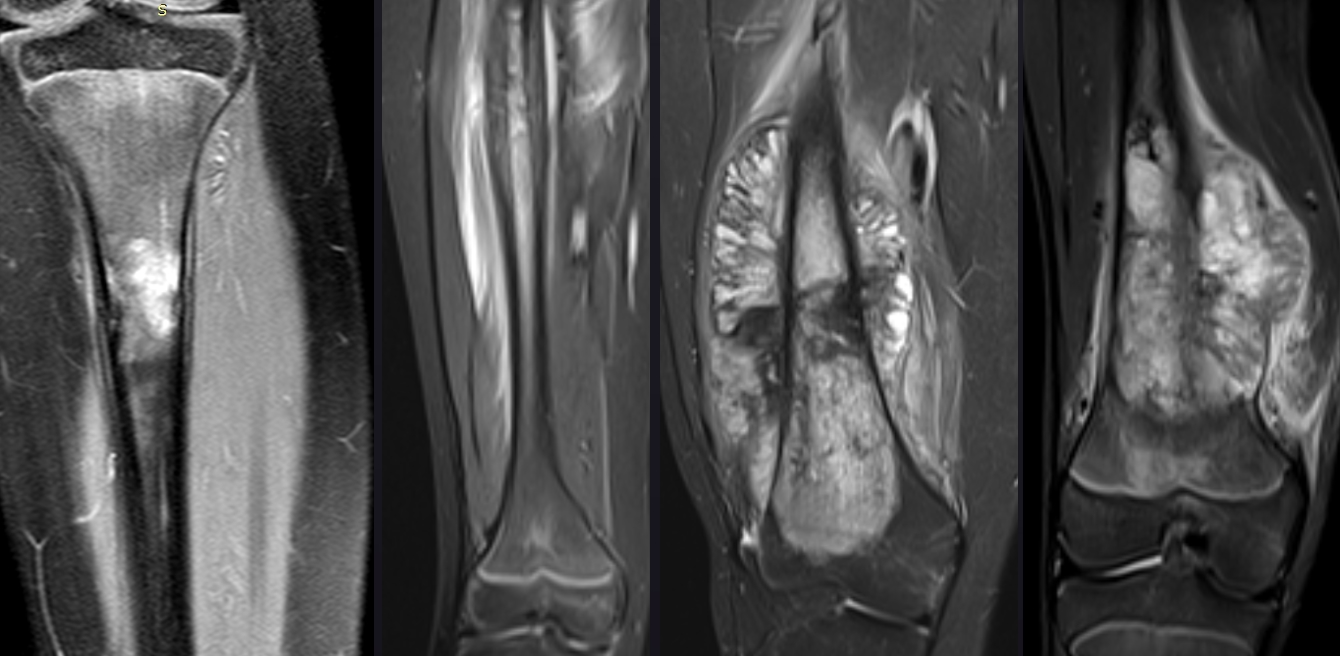

На Т1-зважених зображеннях саркома зазвичай проявляється як область з пониженою інтенсивністю сигналу порівняно з нормальними м'язами. Внутрішня структура пухлини може бути неоднорідною через наявність некротичних зон, крововиливів або фіброзних включень. На Т2-зважених зображеннях більшість сарком демонструють високоінтенсивний сигнал, що відображає підвищений вміст води в пухлинній тканині.

Т1-зважені зображення забезпечують хорошу анатомічну деталізацію та дозволяють оцінити взаємовідношення пухлини з судинно-нервовими пучками.

Т2-зважені зображення з пригніченням сигналу від жирової тканини (STIR або fat-sat) підвищують контрастність та полегшують виявлення патологічних змін.

Внутрішньовенне введення гадолінієвих контрастних речовин суттєво підвищує діагностичні можливості МРТ при саркомах. Характер накопичення контрасту відображає ступінь васкуляризації пухлини та може допомогти в диференціальній діагностиці доброякісних та злоякісних новоутворень.

Саркоми зазвичай демонструють неоднорідне підсилення через наявність некротичних зон та різну ступінь васкуляризації різних ділянок пухлини. Динамічне контрастне підсилення дозволяє оцінити кінетику накопичення контрасту, що може мати прогностичне значення.